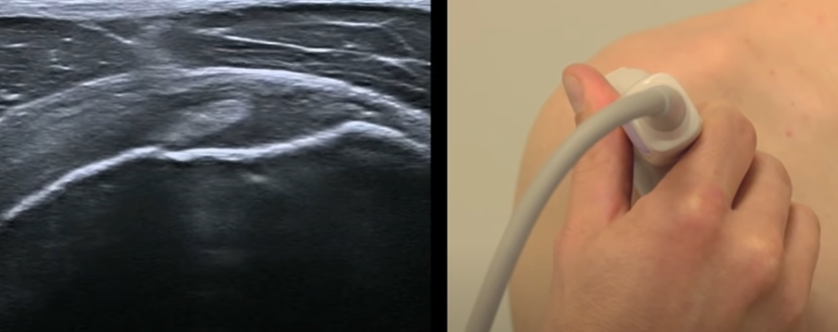

Supra-épineux

- Mains sur les fesses puis adduction (dégage en avant le tubercule majeur qui est sous l’acromion en neutre)

- S’insère sur le tubercule majeur (face horizontale)

- coupe longitidunale (sonde oblique vers le haut et le dedans) avec les fibres du deltodie parralèle au tendon

- coupe axiale (le supra-épineux occuple l’insertion de la surface horizontale, l’infra-épineux la surface oblique du tubercule majeur)

Coupe longitudinale avec fibres parallelles du deltoide

Coupe axiale